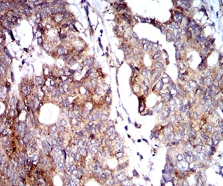

IHC    1/200 - 1/1000